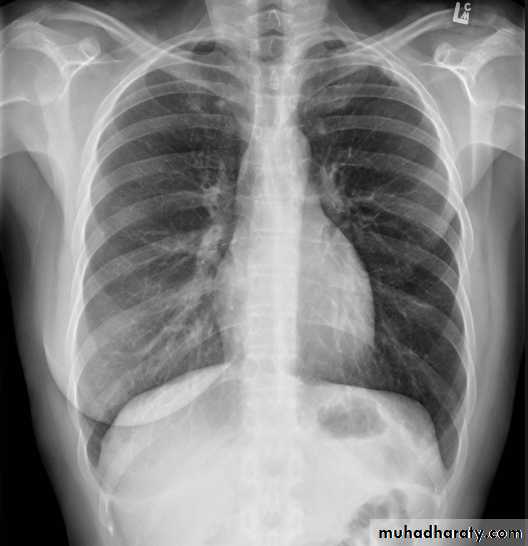

Both should exposed in full insp. And patient in upright position.Films taken in exp. Are difficult to interpret because:

• 1- hazy lung base.

• 2- heart shadow increase in size.

On good insp., the dome of rt. Hemidiaphragm at level of ant. End of 6th rib.